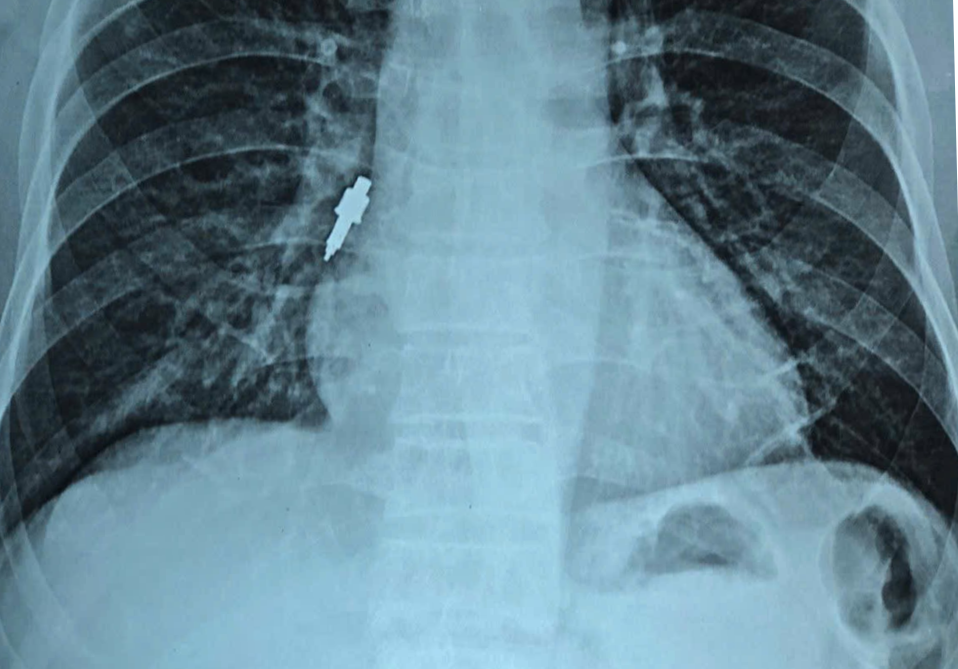

Sau đó, bệnh nhân xuất hiện ho nhẹ kéo dài. Khi cơn ho trở nên dữ dội, gia đình đưa ông đi khám. Kết quả chụp X-quang cho thấy có dị vật nằm trong phế quản phải nên bệnh nhân được chuyển gấp tới Bệnh viện Hữu Nghị.

Tại đây, các bác sĩ quyết định tiến hành nội soi phế quản cấp cứu. Dị vật được xác định bằng inox, bề mặt trơn, đường kính 1cm, dài 2,5cm và mắc sâu vào phế quản phải, kìm sinh thiết thông thường không thể gắp ra.